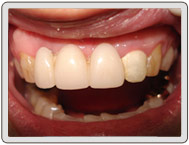

治療後